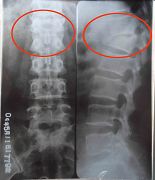

当天半夜我离开家以后,不断更换住处。三月二十九日那天,我刚把房门裂个缝,就见一个贼头贼脑的人正往我这里看,极度的恐惧顿时吓的我不知所措,只想快点离开住处,从窗往外看楼与地面并不高,我就跳了下来,结果受了伤,过路人把我抬到一辆出租车上,当司机知道我的遭遇时他什么都没说,把我送到了一个法轮功学员家。历经一个多月艰难的日子我终于能行走了,那段日子没有医疗(不敢住院怕被绑架),没有家人,只有痛苦和恐惧,若不是有大法的法理、同修的照顾真的很难走过来。后来到医院确诊我的右胳膊肘到手的那段骨头从胳膊肘里撞出来了,胸椎十二节和腰椎一节压缩性骨折,后来成为两椎体融合成一个椎体,当医生看到X光片子惊讶的说:“这是要瘫痪的!”当时腰椎骨折手术得十万余元,我被单位开除,没有生活来源,没钱医治。也只能在弟、妹的援助下做了胳膊的手术,术后胳膊再也不能直伸了,腰部连洗衣服都疼,更不能干重活,终生残疾。

吴旭姝胳膊和腰椎的X光片